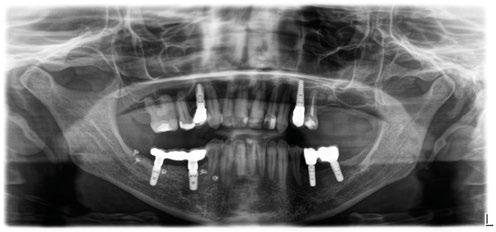

-Estudio radiográfico inicial (ortopantomografía y radiografías periapicales) (Figura 2).

Figura 2. Ortopantomografía inicial.